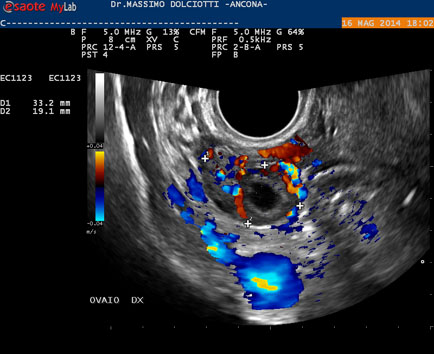

Data inserimento: 19 /05/2014Ecografia del: 16/05/2014 Strumento: Esaote MyLab 50 Gold - Responsabile Linea Cardio Esaote Regione Marche Dr. Franco Fabi Sonda: Endocavitaria Multifrequenza 4-8 MHz Età Paziente: F 27 anni Motivazione dell'esame: amenorrea. Beta HCG = 1.459 mUI/ml. Commento all'esame: le immagini ed il video documentano utero retroverso, con endometrio ispessito e presenza del sacco gestazionale delle dimensioni di 7,6 x 7,2 mm. All'ovaio destro presenza di corpo luteo gravidico con vascolarizzazione aumentata. Conclusioni: gravidanza alla quarta settimana di gestazione (Pregnancy at the fourth week of gestation). Potete esprimere le vostre osservazioni e commenti sul BLOG. Presentazione: Dr. Massimo Dolciotti - Ancona Elaborazione digitale: Andrea Dini - Ancona